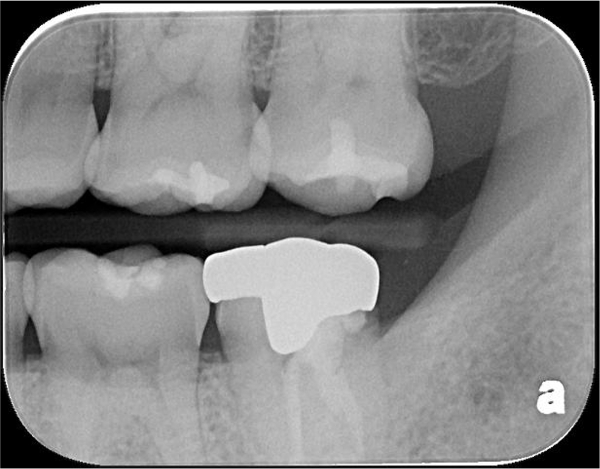

治療前,二次蛀牙

蛀牙未到牙髓